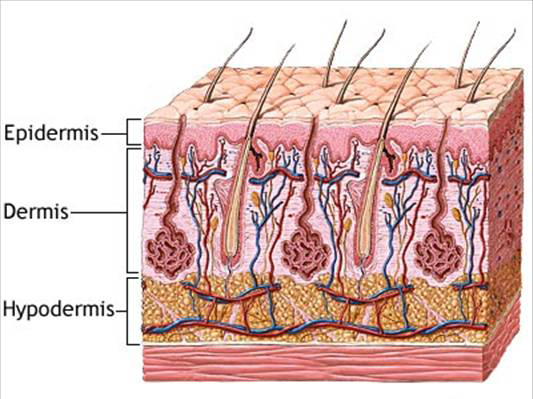

- Excretory organs and their functions e.g. kidney, skin and lungs.

- Waste materials of excretion e.g. carbon (iv) oxide, sweat and urine.